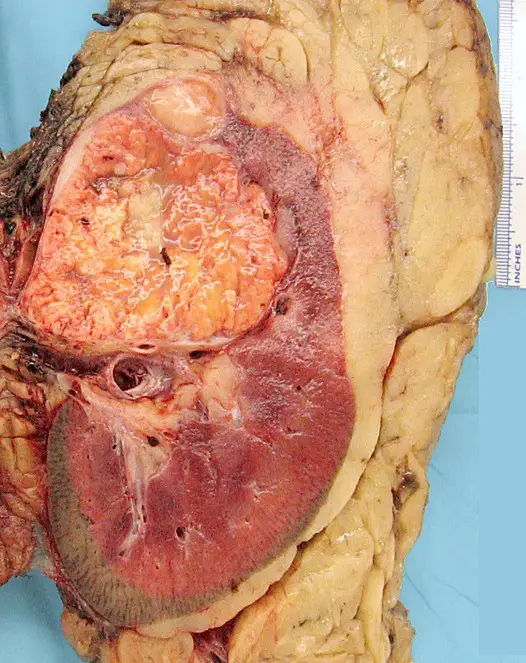

Angiomyolipoma

Angiomyolipoma is a disorder where benign kidney tumors develop.

Angiomyolipoma a tumor made up of blood vessels, smooth muscle, and adipose tissue.

Tuberous sclerosis is associated with angiomyolipoma.